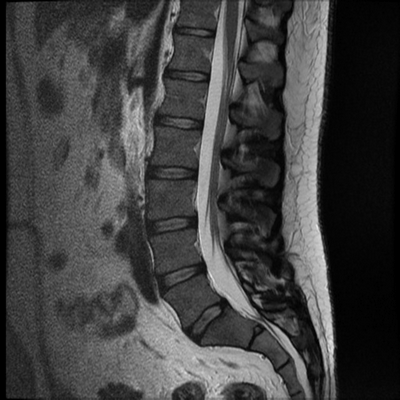

МРТ пояснично-крестцового отдела позвоночника показывает грыжевое выпячивание диска на уровне 5 поясничного и 1 крестцового позвонка, которое оказывает давление на спинной мозг и нервные корешки.

Магнитно-резонансное изображение нормального состояния поясничного отдела позвоночника